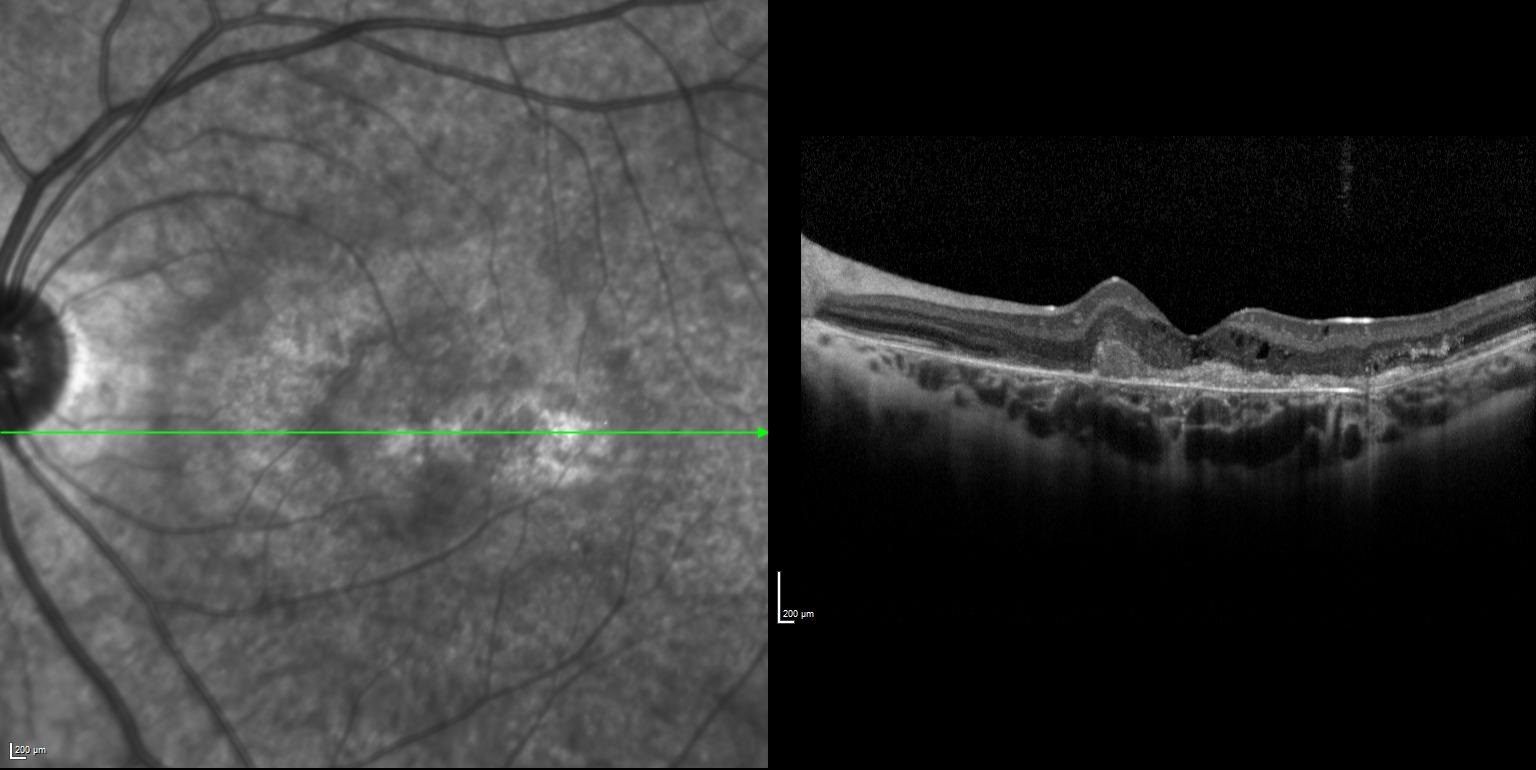

Sol gözde bir haftadır görme azlığı şikayeti başlayan ve görme keskinliği 5 mps düzeyinde olan 15 yaşındaki kadın hasta retina kliniğimize refere edilmiştir. Hastanın renkli fundus ve optik koherens tomografi görüntülerini görmektesiniz. Hastanın doğumunda bir enfeksiyon öyküsü vardır. Sistemik bir hastalığı yoktur. Bu bulgulara göre tanınız nedir? Lütfen cevabınızı aşağıya yazınız.

Bu ay size sol gözde bir haftadır görme azlığı şikayeti başlayan ve görme keskinliği 5 mps seviyesinde olan 15 yaşındaki kadın hastanın renkli fundus ve optik koherens tomografi görüntüleri eşliğinde tanısını sormuştuk.

Tanı: Rubella Retinopati ve maküla/koroid neovaskülarizasyonu’dur.

Konjenital rubella vakaları genellikle katarakt, mikroftalmi, glokom veya pigmenter retinopati ile oftalmoloji bölümüne başvurur. Görme kaybı genellikle katarakt veya eşlik eden mikroftalmi ve nistagmus nedeniyle olur. Pigmenter retinopati tek başına genellikle görme kaybına yol açmaz. Makuladaki retinal tabakaların kronik atrofisine bağlı pigmenter retinopati ile ilişkili olarak gelişen maküla/koroid neovaskülarizasyonu görme kaybına yol açar.

Literatürde rubella retinopatisine bağlı maküla/koroid neovaskülarizasyonu hakkında az sayıda rapor bulunmaktadır. Çalışmalar, kızamıkçık retinopatisine bağlı maküla/koroid neovaskülarizasyonunun yedavi edilmez ise tipik olarak kötü bir görsel prognoza sahip olduğunu göstermiştir. Birkaç istisna dışında, hastalarda diskiform skarlaşma gelişmiş ve görme keskinliği önemli ölçüde azalmıştır.

Literatürde fotodinamik tedavi (PDT) ve anti-VEGF ajanları gibi birkaç tedavi seçeneği tanımlanmıştır. PDT'nin etkili bir tedavi seçeneği olduğu ve neovasküler membranın involüsyonuna, subretinal kanamanın çözülmesine ve görme keskinliğinde iyileşmeye yol açtığı bulunmuştur. Anti-VEGF tedavisi, başka bir seçenektir. Yaygın olarak kullanılan anti-VEGF ajanları bevacizumab, ranibizumab ve aflibercepttir. Anti-VEGF ile maküla/koroid neovaskülarizasyonu'nun önemli ölçüde düzeldiği rapor edilmiştir. Olgumuzda da bu durum izlenmiştir.